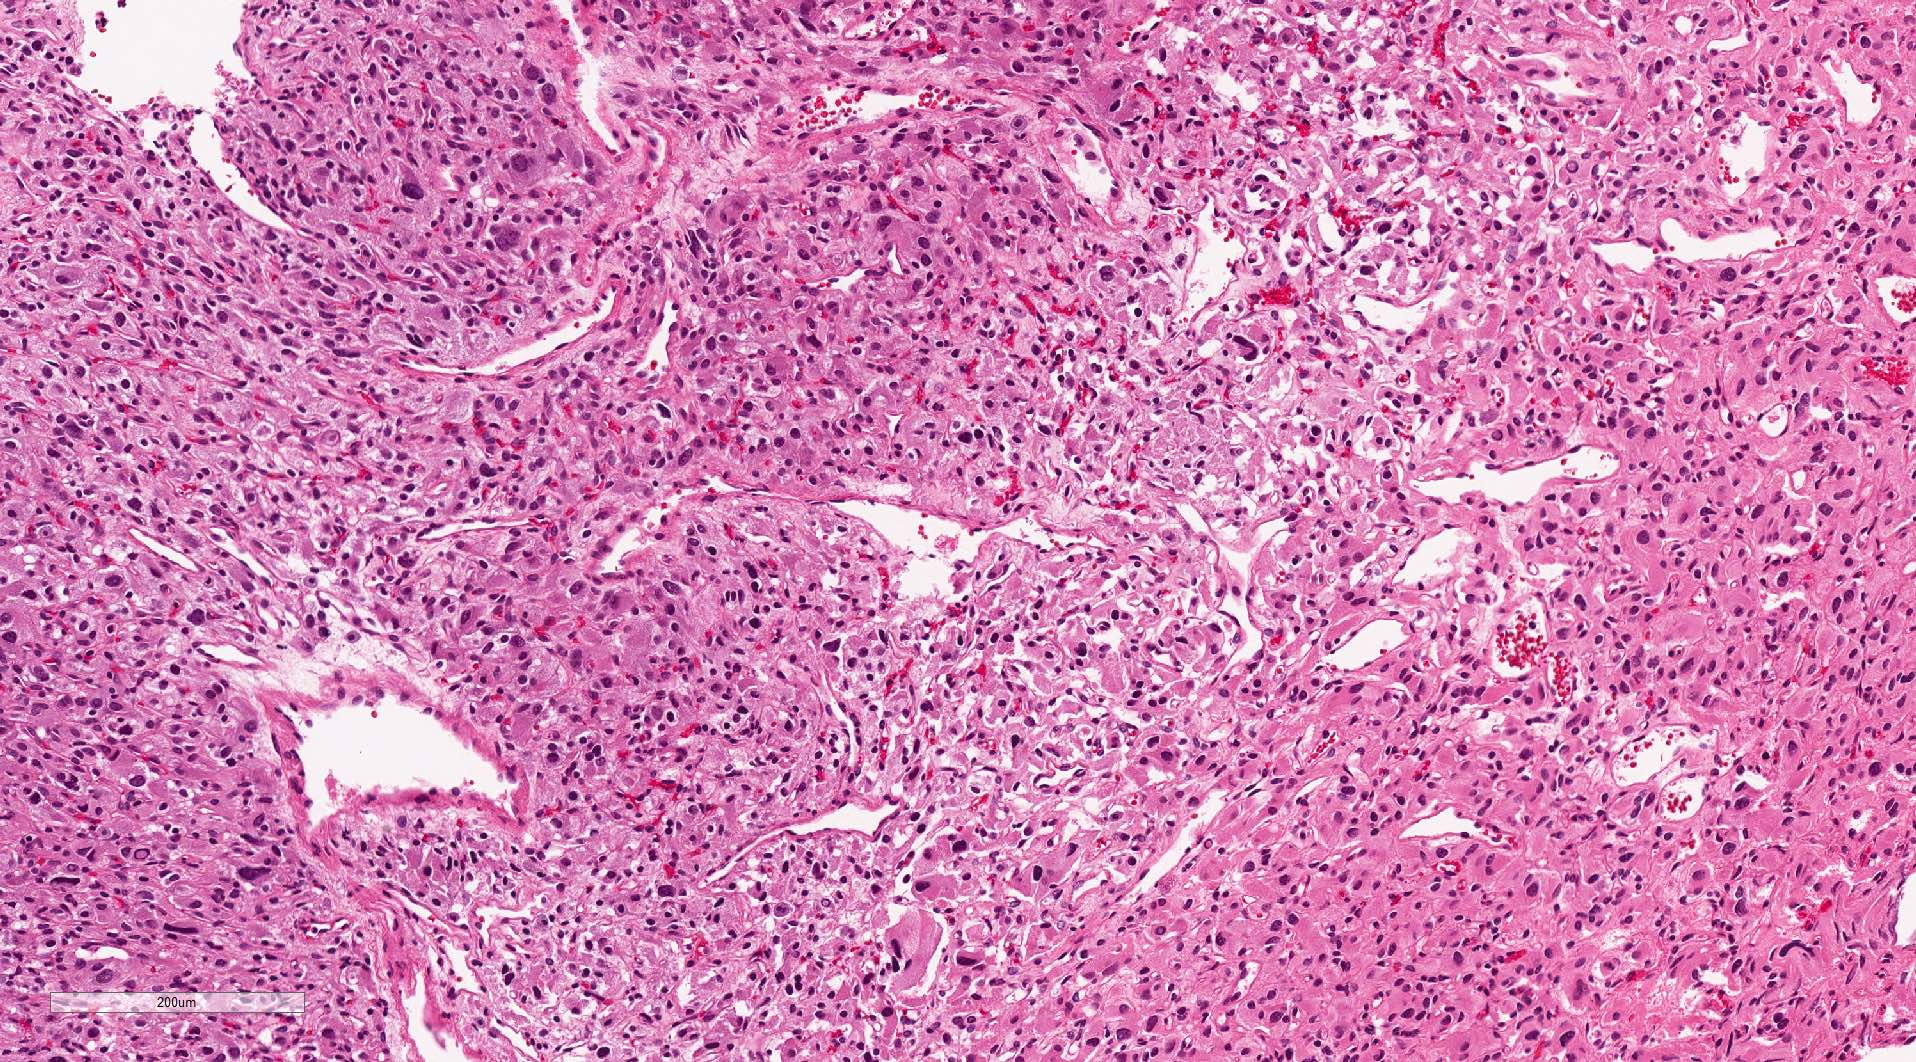

Microscopic (histologic) description

- Typical morphology: epithelioid cells with abundant, eosinophilic / amphophilic, granular cytoplasm and round / ovoid, vesicular / salt and pepper nuclei, arranged in a nested / zellballen pattern and separated by fibrovascular septae with sustentacular cells (Am J Surg Pathol 2004;28:94, World J Clin Cases 2014;2:591, Endocr Pathol 2022;33:90)

- May have focal pleomorphism, nuclear hyperchromasia, low mitotic activity or clear cytoplasm

Microscopic (histologic) images

Contributed by Theodorus H. van der Kwast, M.D., Ph.D., Michelle R. Downes, M.D., Debra L. Zynger, M.D. and David Cohen, M.B.B.Ch., M.D.

- Microscopic description: This specimen shows an unencapsulated, monomorphous population of round tumor cells in a nested / zellballen pattern with delicate vascular septa and intervening extravasated red blood cells. It predominantly involves the lamina propria of the bladder but in 1 tissue piece clearly involves muscularis propria. The tumor cells have abundant amphophilic cytoplasm and vesicular chromatin with occasional small nucleoli. There is no necrosis, diffuse growth pattern or vascular space invasion identified. The mitotic count is (maximally) 1/10 high power fields. Immunohistochemistry shows the tumor cells to be positive for GATA3 with strong and diffuse expression of synaptophysin and chromogranin, as well as retention of SDHB staining. The tumor cells are negative for AE1 / AE3, HMWK and p63. The Ki67 proliferation index is < 1%. S100 shows faint nuclear and cytoplasmic staining with occasional sustentacular cells identified.

- Microscopic description: Sections show unremarkable surface urothelium with a lesion in the deep lamina propria comprised of large eosinophilic cells with hyperchromatic, focally enlarged nuclei with occasional intranuclear inclusions. A fine vascular plexus is identified in some areas. Necrosis and hemorrhage are not identified. Mitotic rate = 1/10 high power fields (field of view [FOV] = 0.55 mm). The lesion extends to the cauterized base of the specimen. Immunostains confirm the lesion expresses synaptophysin, chromogranin and GATA3. SDHB is retained. AE1 / AE3, CD45, p63 and NKX3.1 are negative.